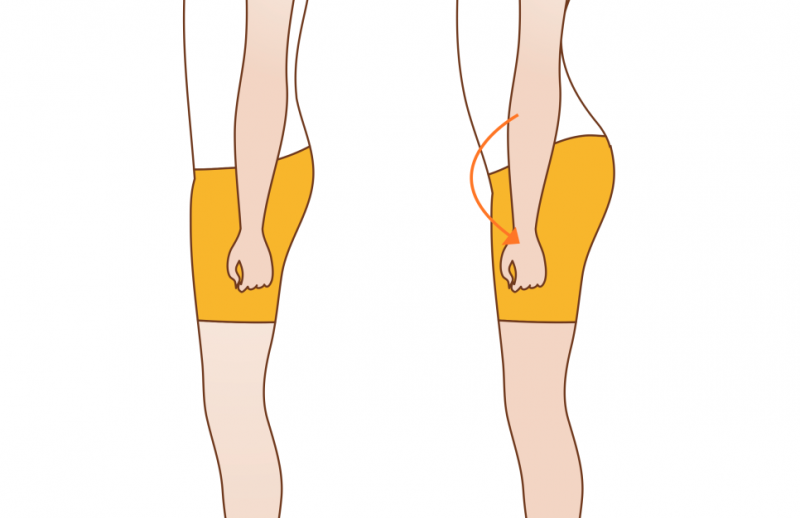

하지만 대부분의 사람들은 뼈가 휘어진게 아니라 대퇴골(허벅지)과 경골(종아리)가 회전이 된 경우입니다.

사진을 보시면 무릎이 안으로 회전된게 보이시나요?

후천적인 요인들에 의해서 대퇴골과 경골이 회전되어 O자 모양이 되거나 X자 모양이 됩니다.

이런 경우에는 부산오다리, 엑스다교정 전문치료를 통해서 회전을 바로 잡아주고 정상정렬로 교정을 하면 바른 다리로 돌아오게 됩니다.

여성분들 중에서 엉덩이를 좌우로 왔다갔다 하며 흔히 말하는 씰룩씰룩 거리며 걷는 분들을 본적이 있나요?

이런분들은 특징적인게 중둔근의 약화로 인해서 골반이 안정화가 되지 못해서 걸을 때 마다 골반이 좌우로 왔다갔다 하게 되는 것입니다.

중둔근이 약해지면 고관절이 안정화가 되지 못하기 때문에 대퇴골이 회전하게 됩니다.